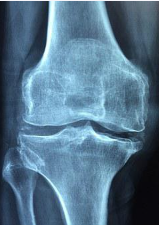

콜라겐의 효능 2. 관절 건강

콜라겐은 관절 연골의 주요 구성 성분 중 하나입니다. 연골은 뼈와 뼈 사이를 완충해주며, 관절 운동을 원활하게 합니다. 콜라겐 부족은 연골의 품질을 떨어뜨려 관절 건강에 부정적인 영향을 미칠 수 있습니다. 단순한 연령보다는 급격한 운동이나 부상으로 인한 연골 손상일 경우 콜라겐 섭취가 더욱 중요합니다. 관절 건강을 유지하기 위해 적극적으로 콜라겐을 섭취하는 것이 좋습니다.